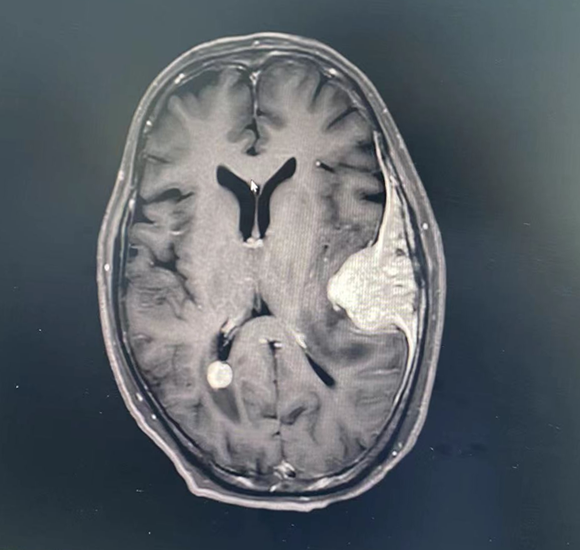

图6

图7

图8

图9

图10

图11

2022.05.27复查发现脑多发转移。